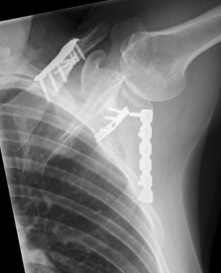

ORIF clavicle

ORIF clavice + scapula

Scapular neck fracture with clavicle fracture